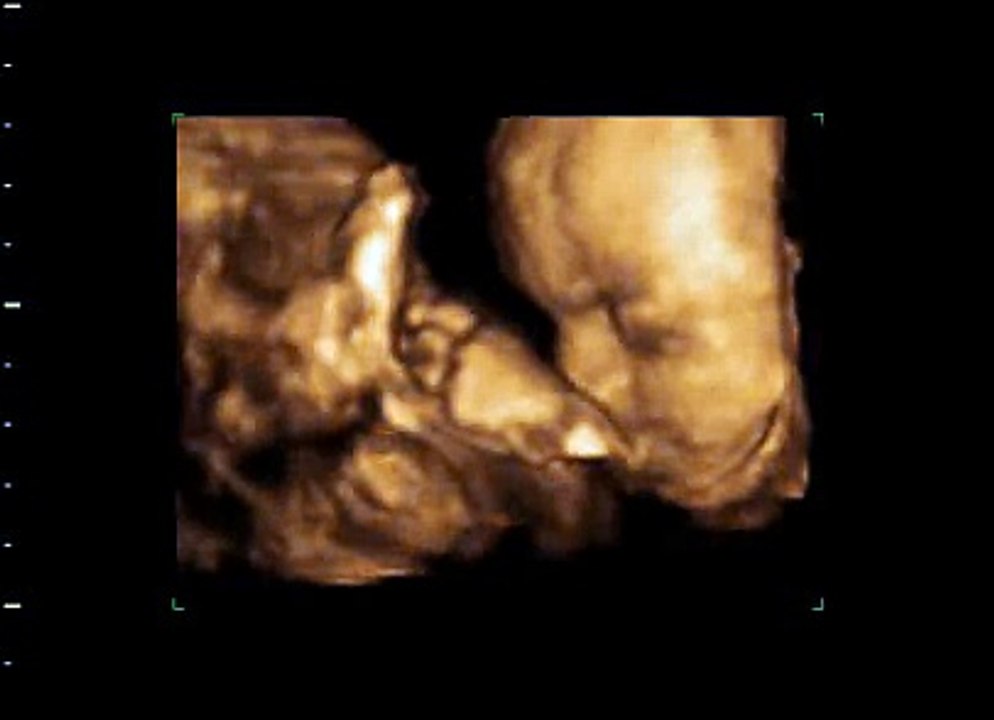

4d Ultraschall 26 Ssw Video Dailymotion

3d 4d Ultraschall Fotogalerie